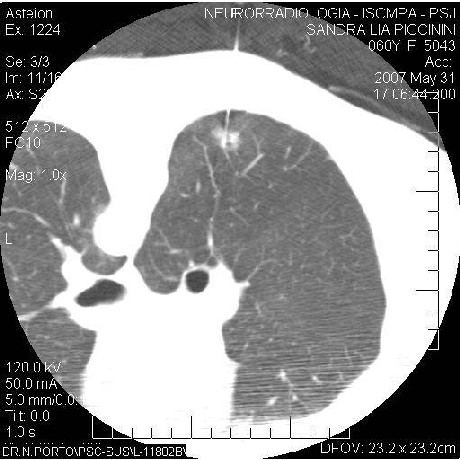

CT thorax partially solid nodule 8mm diameter